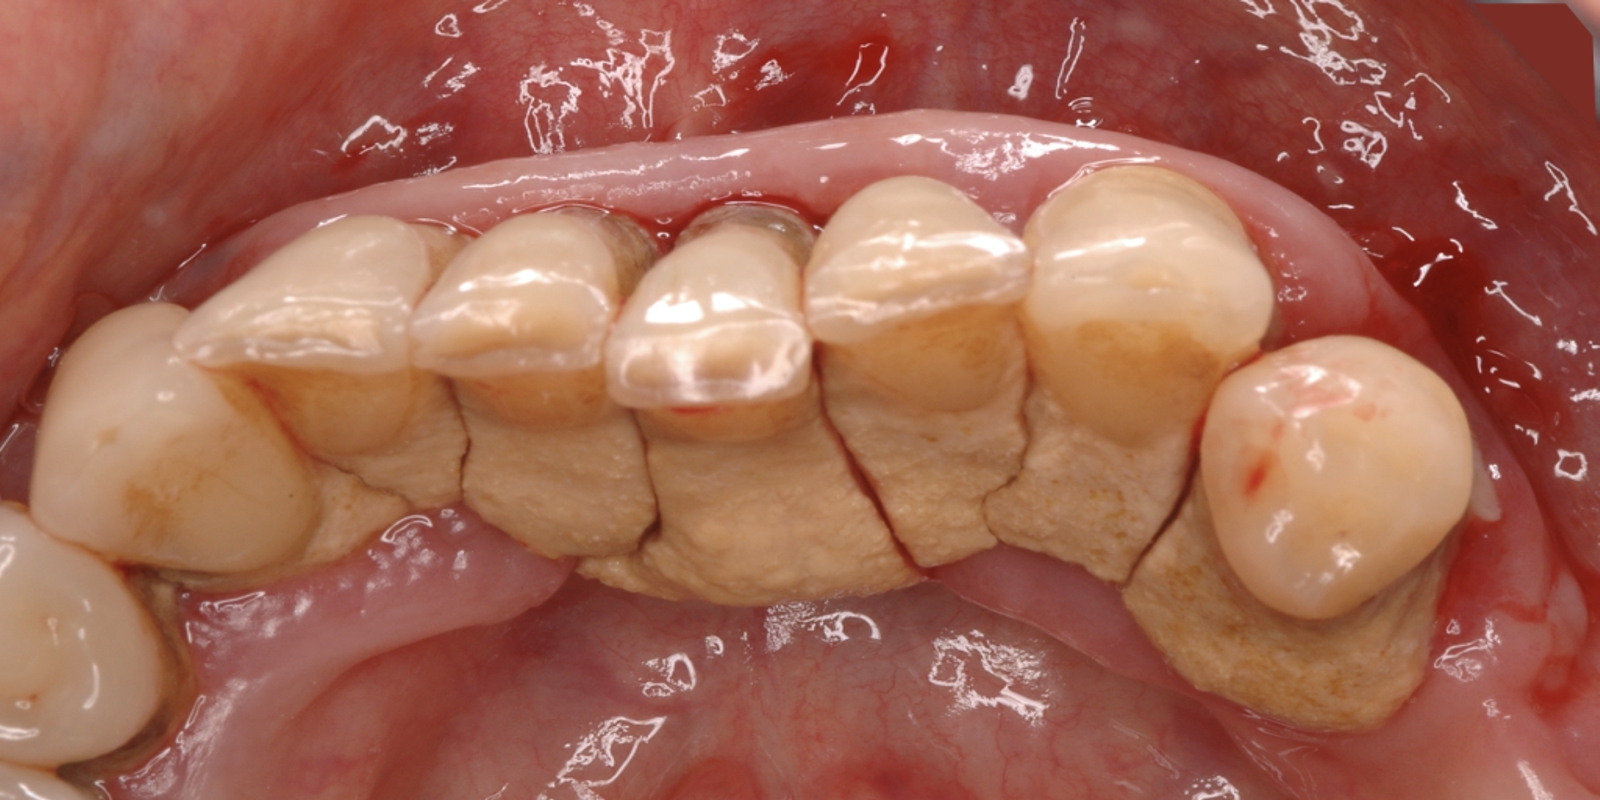

Se la Parodontite non viene trattata precocemente le gengive si allontanano dai denti innescando una cascata di altri problemi dentali. Quando le gengive iniziano a recedere si creano delle tasche, tra i denti e il tessuto gengivale, dove possono accumularsi ancora di più i batteri.

Se non trattata, la Gengivite può progredire nella Parodontite Precoce (2° stadio), che è caratterizzata da una iniziale perdita di osso. I pazienti con malattia parodontale precoce hanno tipicamente una profondità della tasca gengivale compresa tra 4-5 millimetri. Se i pazienti continuano a trascurare la loro salute orale, la Parodontite Precoce può trasformarsi in Parodontite Moderata (3° stadio). In questa fase possono verificarsi livelli moderati di perdita ossea.

Le infezioni nella zona possono creare sanguinamento, produzione di pus e dolore intorno ai denti, la cui mobilità comincia ad aumentare. La recessione della gengiva può inoltre rendere i denti sensibili e soggetti alla carie della radice. I pazienti con Parodontite Moderata hanno una profondità della tasca gengivale di 6-7 millimetri. In questa fase, le infezioni orali possono iniziare a diffondersi nel circolo sanguigno e provocare una risposta infiammatoria in tutto il corpo. Nella naturale evoluzione della Parodontite la fase successiva è rappresentata dalle Parodontite Avanzata (4° stadio), in questa fase, le gengive sono ormai gravemente infette. Le tasche gengivali sono profonde più di 7 millimetri.

I pazienti con Parodontite Avanzata possono soffrire di forti dolori durante la masticazione, alitosi ed un sapore molto cattivo in bocca, a causa dell’infezione.

Poiché le gengive sono regredite in modo significativo, i pazienti in questa fase possono perdere i denti e quelli che non cadono iniziano a spostarsi per riempire i vuoti